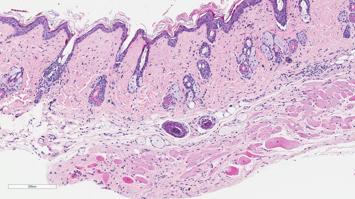

MitmachstationWunderwerk Haut: Was leistet unser größtes Organ?Thema: GesundheitHier erfahren Sie hautnah, aus welchen Schichten und Zellen unsere Haut aufgebaut ist. Fertigen Sie selbst eine Haut an, die Sie beim Kaffee vernaschen können! Lernen Sie über die vielen Aufgaben, die das größte Organ des Menschen erfüllt und erfahren Sie mehr darüber, wie an Universitätskliniken so geforscht wird, dass die Patient:innen am besten und direktesten davon profierten. Besonders für Kinder geeignet!Johannes Kepler Universität Linz17:00 - 23:00 -